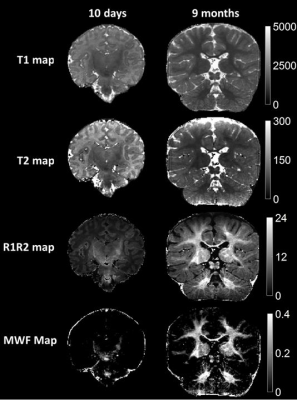

Figure 1: Whole brain T1, T2 and R1R2 maps generated from an MRF scan (pt1, 10 days). Each map defines the appropriate myelination pattern expected in a full-term neonate. The posterior limb of internal capsule (red arrow), lateral thalamus (blue arrow) and coronal radiata (yellow arrow) are best highlighted on R1R2 maps.